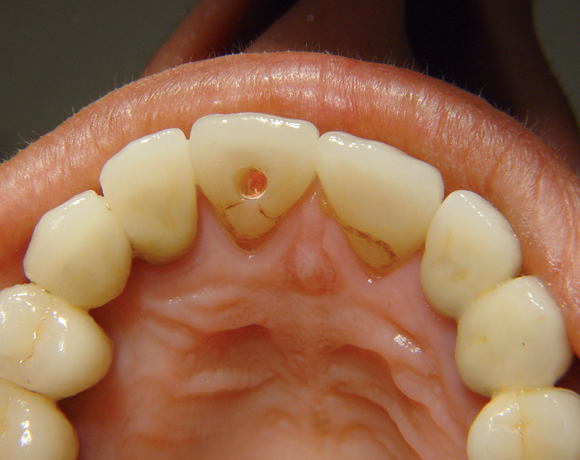

Bei diesem Patientenfall musste nach Neuüberkronung der Frontzähne eine Wurzelbehandlung erfolgen. Um der Gefahr aus dem Weg zu gehen, dass die neue Krone abbricht, da sehr wenig eigene Zahnrestsubstanz nach der endodontischen Behandlung übriggeblieben war, wurde der Zahn nachträglich mit einem Dentinpost versorgt.